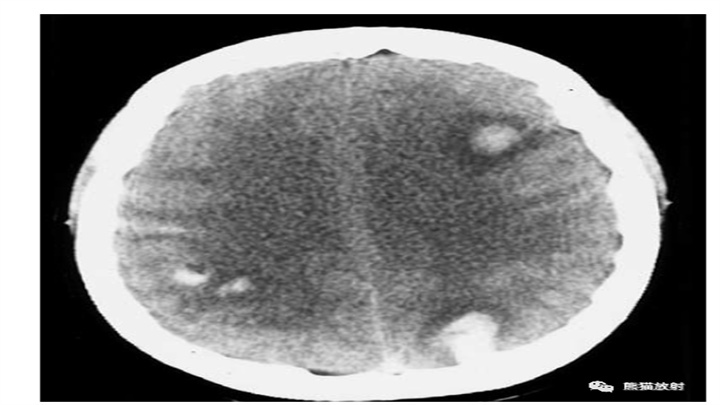

双侧多发脑内出血(2例)。第1例为深部脑白质血肿,左侧为著,密度不均。第2例为乳腺癌多发脑转移合并出血,主要位于灰白质交界处。